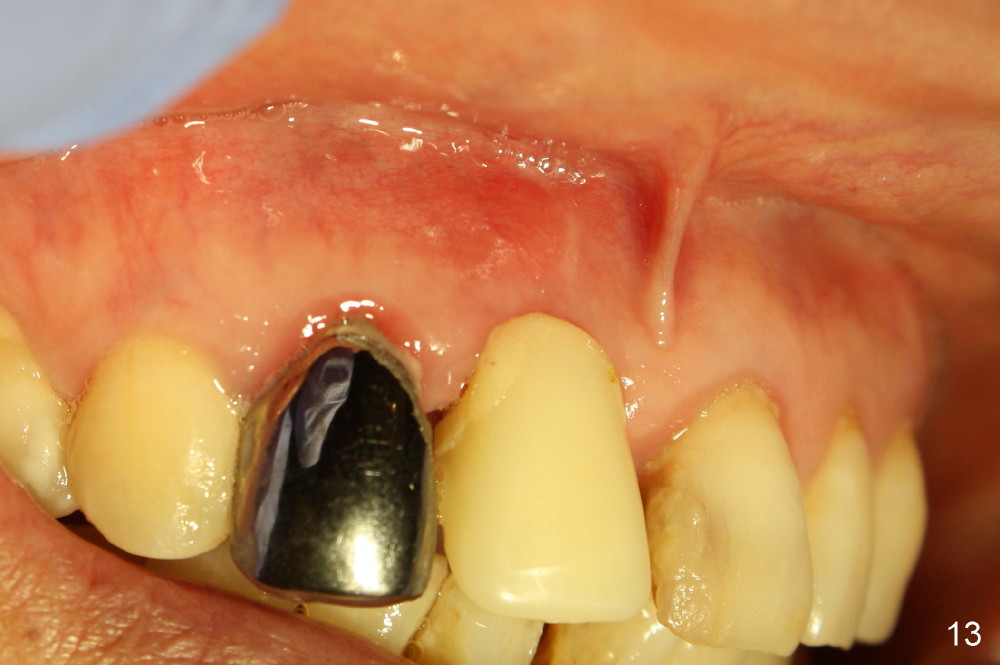

A 64-year-old lady requests replacing #7 and 8 crowns (Fig.1,2). When #8 is extracted, the labial plate is found to be missing (Fig.3). Following 2 mm pilot drill (Fig.4,5 P), 3.8 mm tap drill (Fig.6,7 T) and 4.5x14 mm implant (Fig.8 I) and 4.8 mm abutment (Fig.9 A), corticocancellous bone is harvested from the left tuberosity and placed in the labial gap of the socket (Fig.10 G). Collagen dressing is placed over the bone graft (Fig.11 C). The former is secured in place by an immediate provisional (P).

The patient returns for follow up 8 days postop and the labial margin of the provisional looks long. The metal crown is changed to a provisional at the visit. Eight days later, the provisional at the site of #8 is removed for labial margin trimming; the labial gingiva heals (Fig.14 *). The labial plate remains slightly convex (Fig.15). The labial margin of the provisional at the site of #8 is at the same level of that of #9.